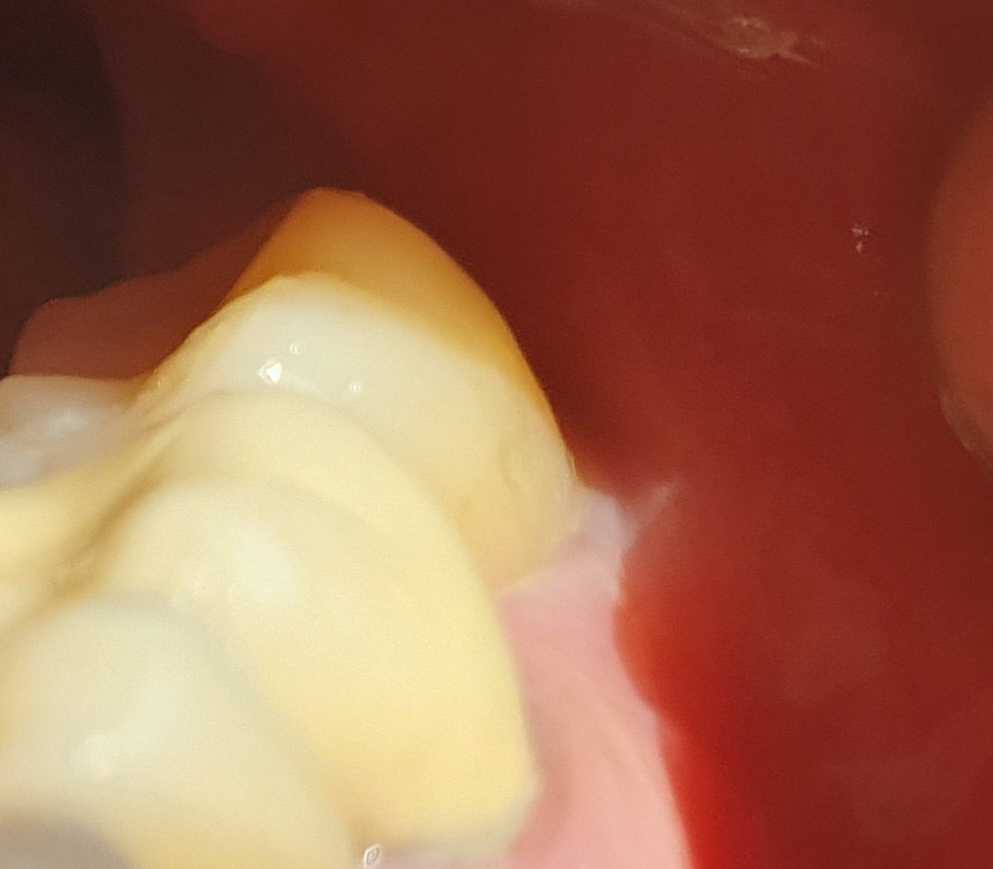

처음 내원해서 진료 받고 스케일링하고 충치치료 했어요. 어금니 충치 레진으로 치료하고 이벤트 가격 8만원 들었어요. 이벤트 덕분에 좋은 가격에 치료 잘 받았어요. 특별히 스케일링 해주신 O수현님 감사해요. 넘 친절하고 일도 꼼꼼하게 잘 하시네요. 감사합니다! 첨부사진: 아랫니 맨 뒤 어금니 레진 충치 치료 후